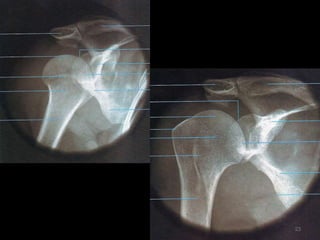

Ombro14

Incidência AP Ombro Rotação Neutra (1)15

16

17

Incidência AP- Ombro Verdadeiro(2)18

Incidência AP- Ombro Rotação Interna e Externa (RI/RE)21

22

23